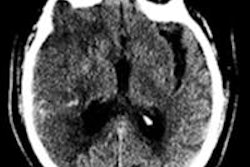

You should also check out this story on the use of CT to predict treatment outcomes in patients with ischemic stroke of the middle cerebral artery, as well as this story about Dr. Ella Kazerooni's Wednesday presentation on whether ultralow-dose CT needs extra validation before its ready for prime time.